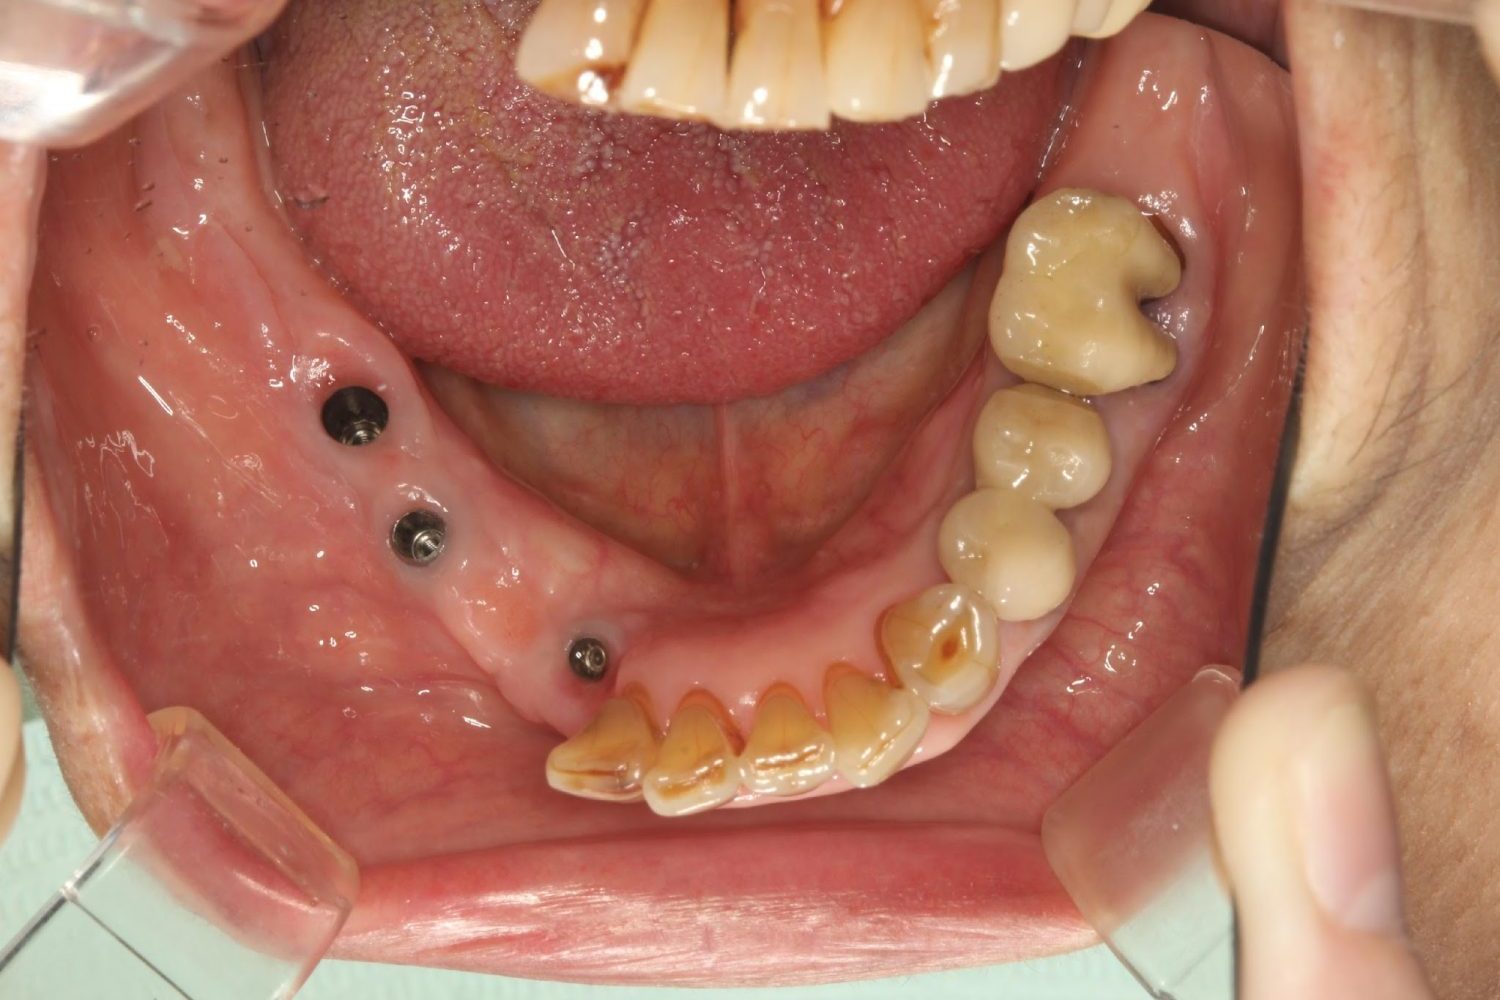

多数歯う蝕および多数歯欠損による咬合崩壊、保存不可能な歯の抜歯により上下無歯顎に。下顎に6本インプラント埋入する事で咬合再構成を行った。

インプラント治療の症例紹介③

Before

After

主訴

むし歯の治療

治療内容

保存不可能な歯の抜歯

下顎にインプラント埋入し咬合再構成

治療費

2,688,400円(税込)

治療期間

14か月

治療回数

21回

想定されたリスク

※上部構造の形態が複雑になるため清掃が難しくなる。インプラント周囲炎の恐れがありました。